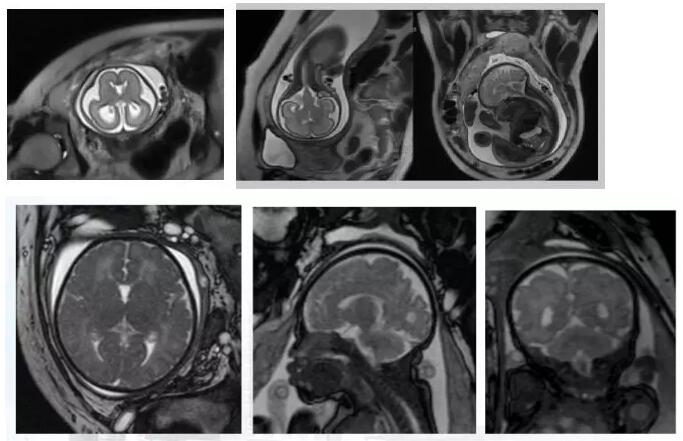

磁共振图像可以在各个方位看到宝宝的颅脑,还能看到宝宝撅起的小嘴。

磁共振图像可以在各个方位看到宝宝的颅脑

用同样方法做出来的腰骶丛神经磁共振图像,结构清晰,病变明显